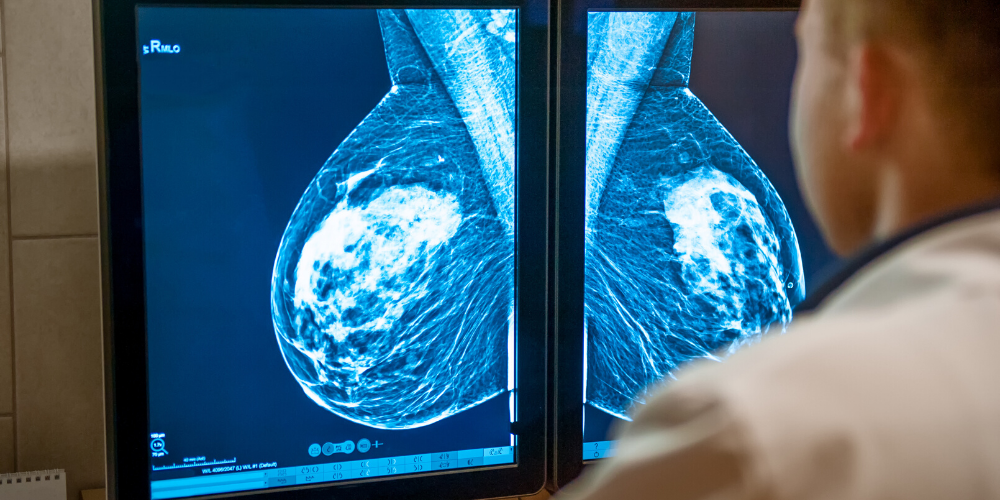

How Mammography Works

• How it works: Mammograms are breast screenings that use X-ray imaging to identify changes in breast tissue. These can identify changes that may indicate growths or early signs of breast cancer. These changes may not be caught with self-detection, MRIs, or ultrasound.

During a mammogram, breasts are flattened between two surfaces to thin out tissue and capture digital imagery. The images are then reviewed by a specialized doctor called a radiologist. If an area of concern is identified, a diagnostic ultrasound may be necessary.

• Strengths: Mammograms are used as screening tools and can detect early calcifications and subtle changes not visible by touch or ultrasound. The role of a screening tool (mammogram) is to detect risk factors or potential cancerous growths early on before progression (while they are still asymptomatic).

• Limitations: Less effective in women with dense breast tissue. In addition, mammograms do not provide diagnostic certainty.